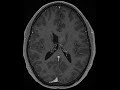

Central Neurocytoma

There is a mildly enhancing T2/FLAIR hyperintense mass in the left lateral ventricle abutting the septum pellicudum. This was a central neurocytoma at pathology, which more classically has a "bubbly" T2 appearance, but remains the leading imaging differential diagnostic consideration in this case.